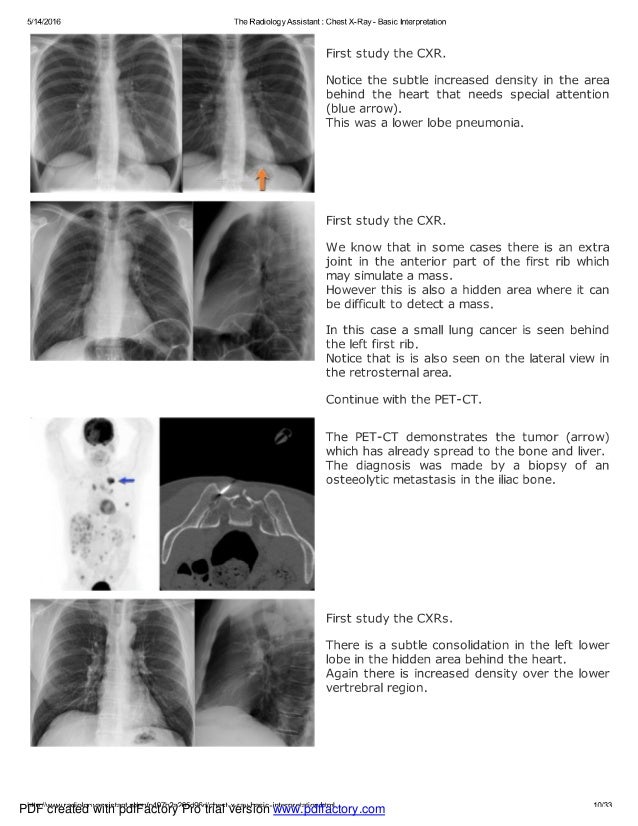

Chest x ray basic interpretation Examples Of Chest X-Ray Interpretation Doctors typically use this procedure to help diagnose breathing difficulties, a bad or. 159 rows — litfl 100 (150) cxr quiz. — document your interpretation of the cxr: In fact every radiologst should be an. — it is therefore important that you can confidently assess a chest radiograph and detect abnormalities, especially those that are life. It. Examples Of Chest X-Ray Interpretation.